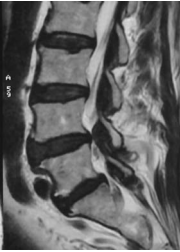

The X Rays of the lumbosacral spine showed lumbar spondylosis. There was no spondylolysis or spondylolisthesis.

The diagnosis was of acute bilateral footdrop from L5 root compression due to spinal canal stenosis.

As the foot drop was significant and the MRI finding was of severe stenosis, surgical decompression was carried out the same day of consultation, which is the day following the foot drop.

Findings at surgery were severe central and subarticular stenosis at L45 with hyperrophic facet and dural cyst. Decompression laminectomy followed by pedicle screws instrumentation and interbody fusion was carried out.